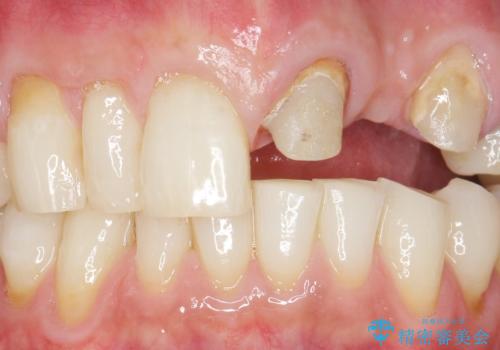

- ブリッジの支台歯であった左上の犬歯が折れたことを主訴に来院された患者様です。

犬歯は歯ぐきの奥深くまで割れており保存不可能な状態でしたが、どうしても抜きたくないとのことでした。

歯を牽引し健全歯質を歯肉縁上まで引き上げ、歯の保存を試みることにしました。